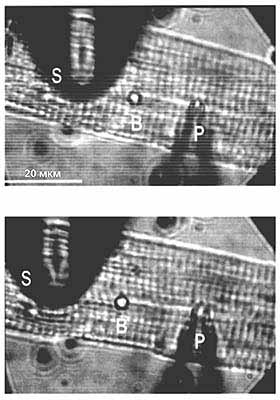

Микрофотографии изолированного кардиомиоцита. Вверху: клетка, к мембране которой подведены две микропипетки - регистрирующая (Р) и растягивающая (S), - но ни одна еще не задействована; внизу - растянутый кардиомиоцит. Для визуального слежения за растягиванием между пипетками помещен резиновый шарик (B). Через первую пипетку, которая содержит электролит, подается отрицательное давление такой силы, чтобы прорвать мембрану и установить контакт между содержимым клетки и электролитом, после чего и регистрируется ионный ток. Второй пипеткой клетка только растягивается. По результатам измерения силы тока до и после механического воздействия можно судить о влиянии последнего на генерацию ионного тока клетками сердечной мышцы.

Поскольку эффект растяжения ткани миокарда блокировался ионами гадолиния - ингибиторами механочувствительных каналов, - напрашивался вывод об их участии в описанных событиях [5]. Но чтобы доказать это, необходимо было исследовать ионные токи и сами МСК не на ткани сердца, а на отдельных жизнеспособных клетках. Для растяжения единичного кардиомиоцита и измерения в нем тока, мы разработали специальный прием, который и использовали в дальнейших экспериментах на изолированных клетках из желудочков сердца [4].